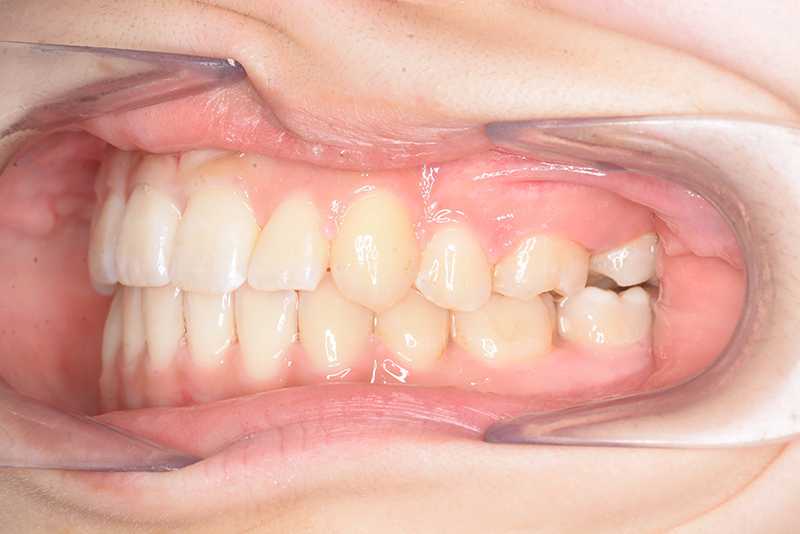

| 口腔内所見 | over jet 3.8mm、over bite 30mm、臼歯関係I級、上下顎前歯部に叢生が認められ、下顎正中は右側へ4.5mm偏位していた。左上5はCRの治療痕が認められた。 |